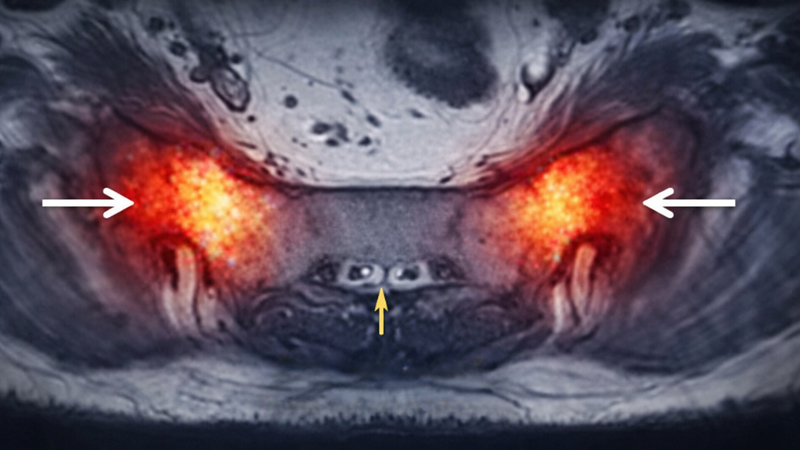

Hình ảnh MRI viêm khớp cùng chậu

MRI là phương pháp nhạy nhất để phát hiện viêm khớp cùng chậu ở giai đoạn sớm, đặc biệt khi X-quang chưa có biến đổi rõ ràng. Những đặc điểm thường thấy trên MRI gồm:

• Phù tủy xương: Dấu hiệu sớm của viêm, thể hiện dưới dạng vùng tăng tín hiệu.

• Viêm màng hoạt dịch: Mô mềm quanh khớp có dấu hiệu viêm.

• Tổn thương sụn khớp: Có thể phát hiện trước khi thấy trên X-quang.

• Tích tụ dịch khớp: Cho thấy phản ứng viêm đang diễn ra.

Theo nhiều nghiên cứu, MRI được xem là tiêu chuẩn quan trọng trong chẩn đoán sớm viêm cột sống dính khớp liên quan đến khớp cùng chậu.

Viêm khớp cùng chậu có thể gây phù tủy xương